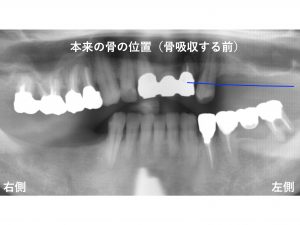

上顎左側の骨の状態をみていきましょう!

本来顎の骨は、

以下の青線 まで存在しています。

しかし、本ケースでは、骨吸収 が大きく起こっていました。